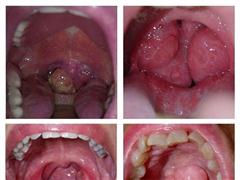

Ung thư đường tiêu hóa là bệnh do sự xuất hiện của các khối u ác tính xuất phát từ trong lòng hoặc thành đường tiêu hóa. Hệ thông tiêu hóa được tạo thành bởi một hệ thống ống rỗng (thực quản, dạ dày, ruột non, ruột thừa, đại tràng, trực tràng và hậu môn) và một vài cơ quan đặc khác (chẳng hạn như tụy, gan và mật). Ung thư có thể phát triển ở bất kỳ cơ quan bộ phận nào, tuy nhiên, nguy cơ cao nhất là thực quản, dạ dày, đại tràng, trực tràng và hậu môn.

Ung thư mũi họng Ung thư mũi họng

Y dược phúc nguyên chuyên điều trị  u bướu, ung bướu, nhọt độc bằng bài thuốc dân tộc lá rừng. Nhiều đời là khắc tinh của các bệnh khối...